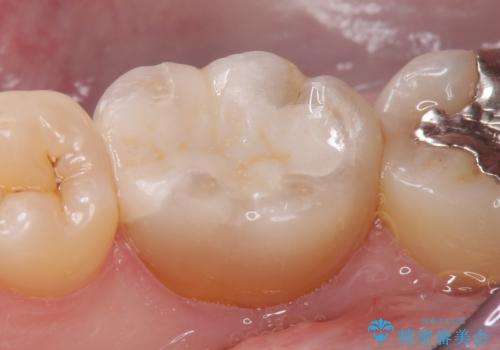

- 右下6番目の歯の舌側に虫歯があるので治療して欲しいといらっしゃった方の症例です。

古い銀歯及び虫歯を除去後、セラミックインレーにて修復を行いました。

当院のセラミックインレーはemaxという強度と審美性に優れた材料を使用しています。

またプレス方式でインレーを製作しているため、削り出しで製作するCADCAMより優れた適合性も持ち合わせており、虫歯が再発しにくい修復物です。